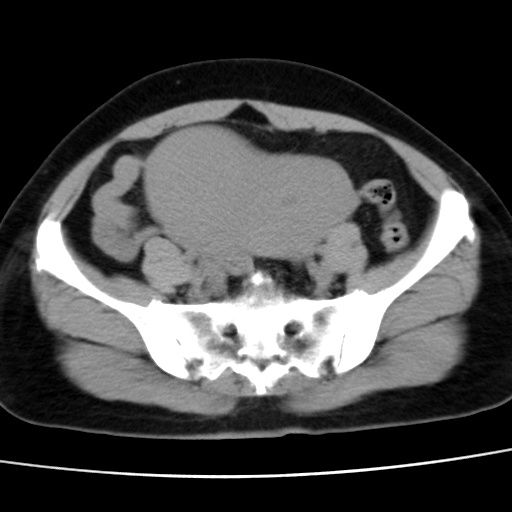

子宫多发肌瘤吗

多发性子宫肌瘤.

考虑多发子宫肌瘤,子宫直肠窝双囊性占位,另直肠周围脂肪密度增高,不知有何病史

支持考虑多发子宫肌瘤~!子宫直肠陷凹积液?

支持考虑多发子宫肌瘤~!子宫直肠陷凹积液!

子宫肌瘤,宫体部后方见液性密度影,是肠道还是子宫与直肠陷窝积液不好说,我觉得它的位置有点高

支持考虑多发子宫肌瘤!子宫直肠陷凹积液!

患者发热,而子宫直肠窝液性灶有明显边缘且局限且囊性,不除外为包裹性积液或脓肿

支持考虑多发子宫肌瘤,子宫直肠陷凹积液可能。

考虑多发子宫肌瘤

1)考虑子宫肌瘤可能性大。2)子宫后方囊性占位性病变,不排除卵巢囊肿可能。

考虑多发子宫肌瘤。子宫后方囊性占位性病变,不排除卵巢囊肿可能。